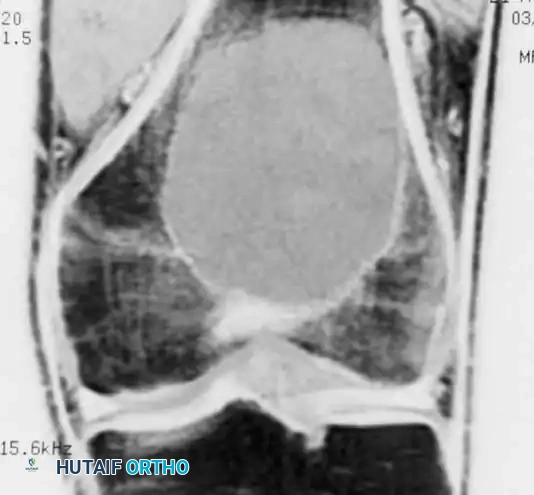

MRI is indispensable for determining the exact intraosseous extent of the tumor, evaluating the integrity of the subchondral bone, and identifying soft-tissue extension.

Coronal MRI demonstrating a large, eccentrically located giant cell tumor in the distal femur extending to the subchondral plate.

- Signal Characteristics: The lesion typically demonstrates low-to-intermediate signal intensity on T1-weighted images and heterogeneous high signal intensity on T2-weighted images.

- Secondary Aneurysmal Bone Cyst (ABC): MRI is highly sensitive for detecting fluid-fluid levels, which are indicative of a secondary ABC—a phenomenon occurring in up to 20% of GCT patients.